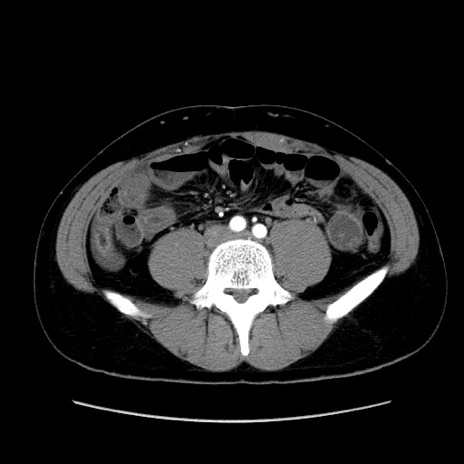

冠状断像

症例36(横断像)

【症例】20歳代 男性

【主訴】心窩部痛

【現病歴】今朝より上腹部痛あり。一旦軽快していたが再度出現したため救急要請。昨日夕に白身の魚を含む刺身を食べた。

【身体所見】BP 136/89mmHg、HR 74/min、BT 37.0℃、腹部:膨満、軟、心窩部に圧痛あり。反跳痛なし、筋性防御なし、腸雑音やや亢進あり。

【データ】WBC 17700、CRP 0.48